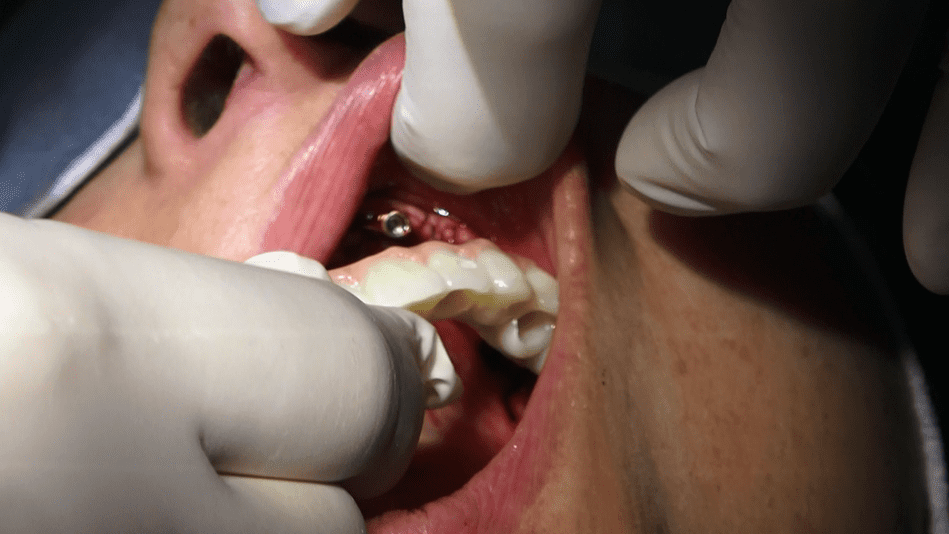

• Il video documenta ogni fase dell’intervento, dalla progettazione personalizzata della griglia sottoperiostea all’applicazione dei singoli impianti e, infine, alla realizzazione di una protesi dentale a carico immediato.

• Durante l’intervento chirurgico, la griglia sottoperiostea viene posizionata direttamente sull’osso mascellare, fornendo un supporto stabile per gli impianti dentali.

• Una delle caratteristiche distintive di questa tecnica è il carico immediato. Subito dopo l’inserimento della griglia e degli impianti, viene applicata una protesi dentale fissa provvisoria, consentendoti di avere denti fissi fin dalla stessa giornata dell’intervento.